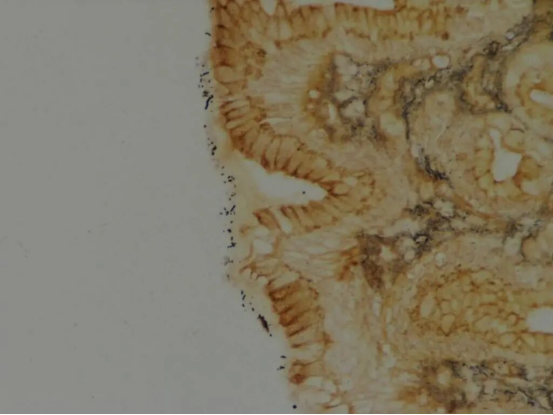

2.HP的IHC染色法:

IHC染色后,HP菌体和菌体成分呈棕褐色阳性着色,与苏木精复染后的淡蓝色背景相比,相较与HE染色,易于观察判断(图3)。

图3_胃镜活检组织HP染色,菌体呈棕褐色,背景呈淡蓝色(40X)